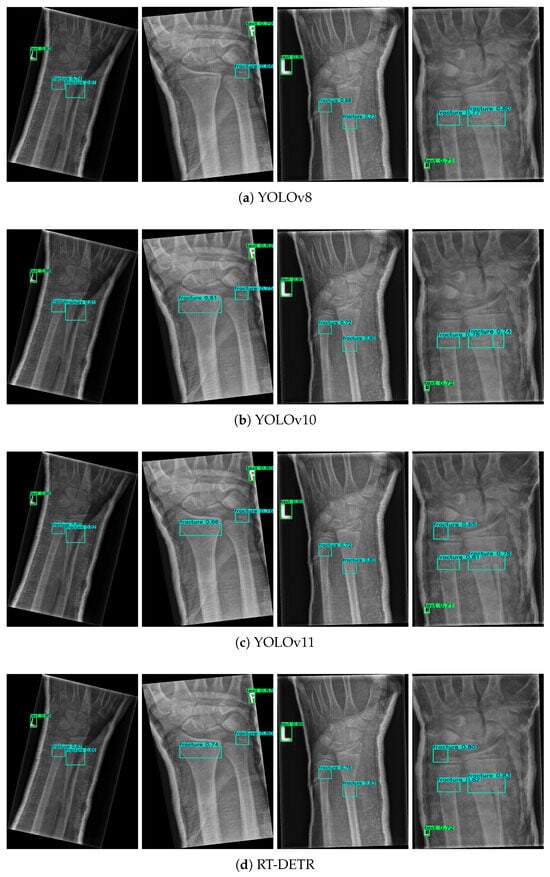

3.1. Main Performance Evaluation

| Models | Parameters | Recall | mAP@50 | mAP@50-95 | F1-Score | Jaccard Index |

|---|---|---|---|---|---|---|

| YOLOv8 | 3.1 | 0.510 | 0.537 | 0.328 | 0.61 | 0.439 |

| YOLOv10 | 4.3 | 0.520 | 0.540 | 0.338 | 0.621 | 0.45 |

| YOLOv11 | 5.1 | 0.520 | 0.542 | 0.336 | 0.621 | 0.45 |

| RT-DETR | 8.9 | 0.530 | 0.533 | 0.340 | 0.624 | 0.454 |

| Ours | 2.8 | 0.550 | 0.611 | 0.402 | 0.655 | 0.487 |